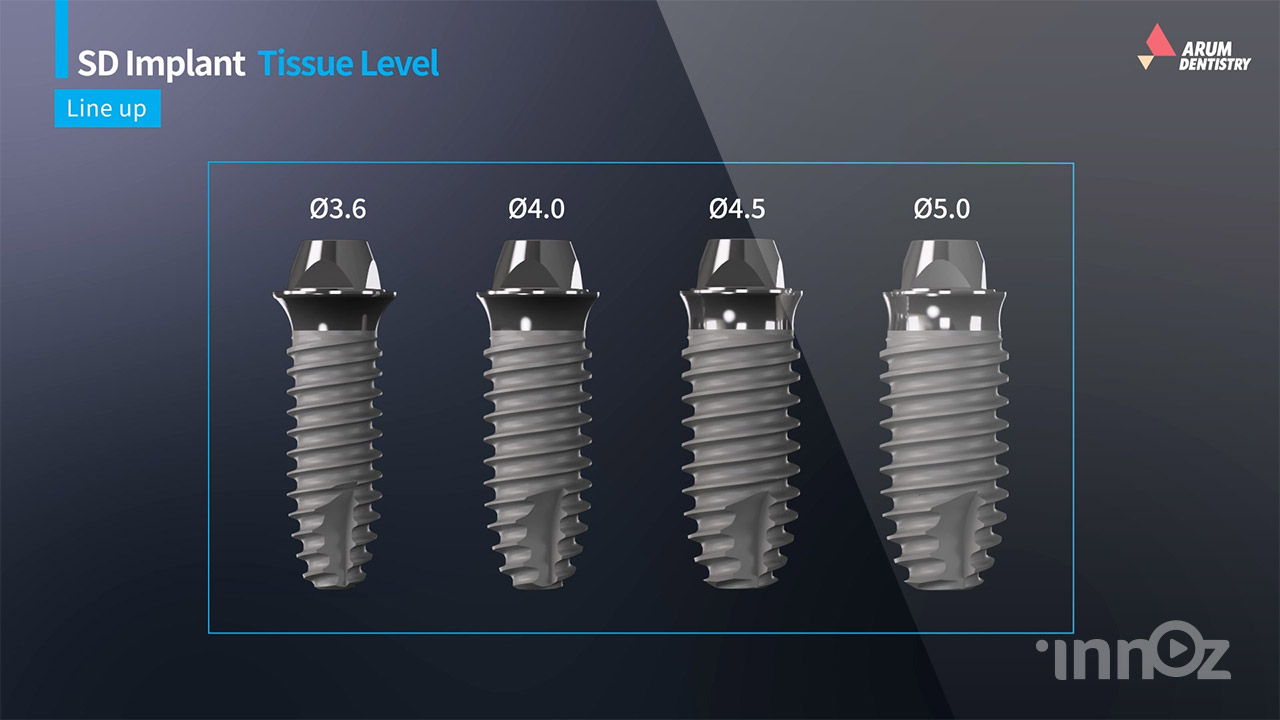

아름덴티스트리

아름덴티스트리